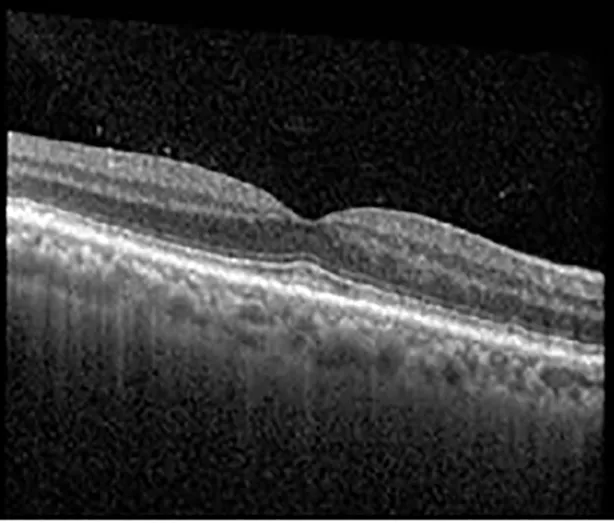

The patient began treatment with oral pemigatinib daily and was followed up for an ophthalmic examination during the second treatment cycle approximately 5 weeks into the treatment process. The patient had at this stage received 28 doses of 13.5 mg per day, which was administered in cycles of 14 on-days and 7 off-days, and had no visual or ophthalmic complaints. The non-corrected VA was OD 20/30 + 1 and OS 20/20. The OCT examinations revealed subfoveal SRF bilaterally. The fundus examination was otherwise unremarkable outside the patient’s prior documented peripheral drusen. Repeat autofluorescence was overall unchanged, though a slight hypofluorescent ring may be visualized in Figure 2. The current pemigatinib protocol recommendation for asymptomatic patients suggests no dose modification; however, with worsening presentation or positive symptoms, it is recommended to withhold pemigatinib. After discussion with the patient’s oncologist, it was decided to continue the medication at this time. Serial monitoring of the patient’s symptoms, vision, and SRF were conducted on specific days during active treatment cycles and days off-cycle to monitor the SRF. Subsequent evaluations demonstrated complete resolution of SRF while off-cycle, and asymptomatic re-accumulation of fluid while on-cycle with varying levels of VA. (Table 1) As we see demonstrated in the table below, in the later stages of the active cycles, such as day 13 of 14 of cycle 2, day 13 of 14 of cycle 3, day 13 of 14 of cycle 4, and day 14 of 14 on cycle 5, the patient’s VA showed no correlative changes based on the presence of SRF. The fluctuations in the patient’s VA certainly occurred, but were likely to be secondary to surface changes, as certain off-cycle days actually presented with lower acuities than days when the SRF was present on OCT examination.

| Cycle, day, on/off | VA OD; OS | CMT OD; OS | OCT OD | OCT OS |

| Cycle 2, day 13/14, on | 20/30+1; 20/20 | 365; 355 | ![]() | ![]() |

Highlights the visual acuity, central macular thickness, and the physical OCT of the macula for this patient in both the right and left eyes during various stages of the patient's chemotherapy treatment cycle.